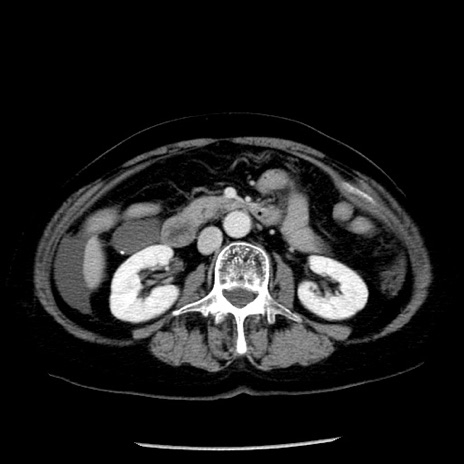

症例13(横断像)

【症例】70歳代女性

【主訴】腹痛、嘔吐

【現病歴】15時間程前(昨晩)より腹痛あり。今朝になっても症状の改善なく、嘔吐あり。腹痛も増悪あり、救急外来受診。

【既往歴】子宮癌全摘術後

【身体所見】意識清明、BP 121/72mmHg、P 74bpm、SpO2 100%(RA)、腹部:平坦・軟、腸雑音ほぼ聴取せず。下腹部・心窩部・臍左上に圧痛あり。反跳痛なし。

【データ】WBC 10600、CRP 0.15